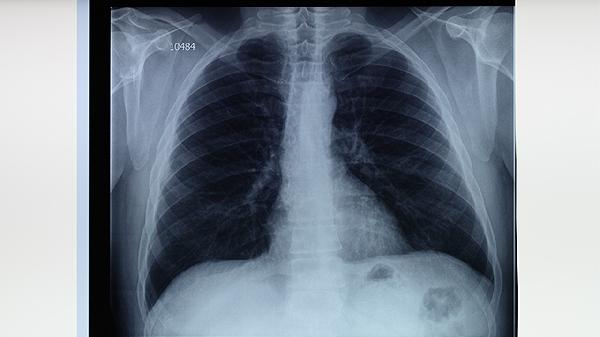

潛伏性結(jié)核感染的主要風險在于其隱蔽性。感染者可能長期攜帶結(jié)核桿菌而不自知,細菌在體內(nèi)持續(xù)存在但未激活。這類人群通常結(jié)核菌素試驗或干擾素釋放試驗呈陽性,但胸部影像學檢查無活動性病變。由于缺乏咳嗽、發(fā)熱、盜汗等典型癥狀,患者往往不會主動就醫(yī),導致診斷延遲。當免疫力下降時,休眠的細菌可能重新活躍并發(fā)展為活動性肺結(jié)核,此時不僅治療難度增加,還可能已傳播給密切接觸者。